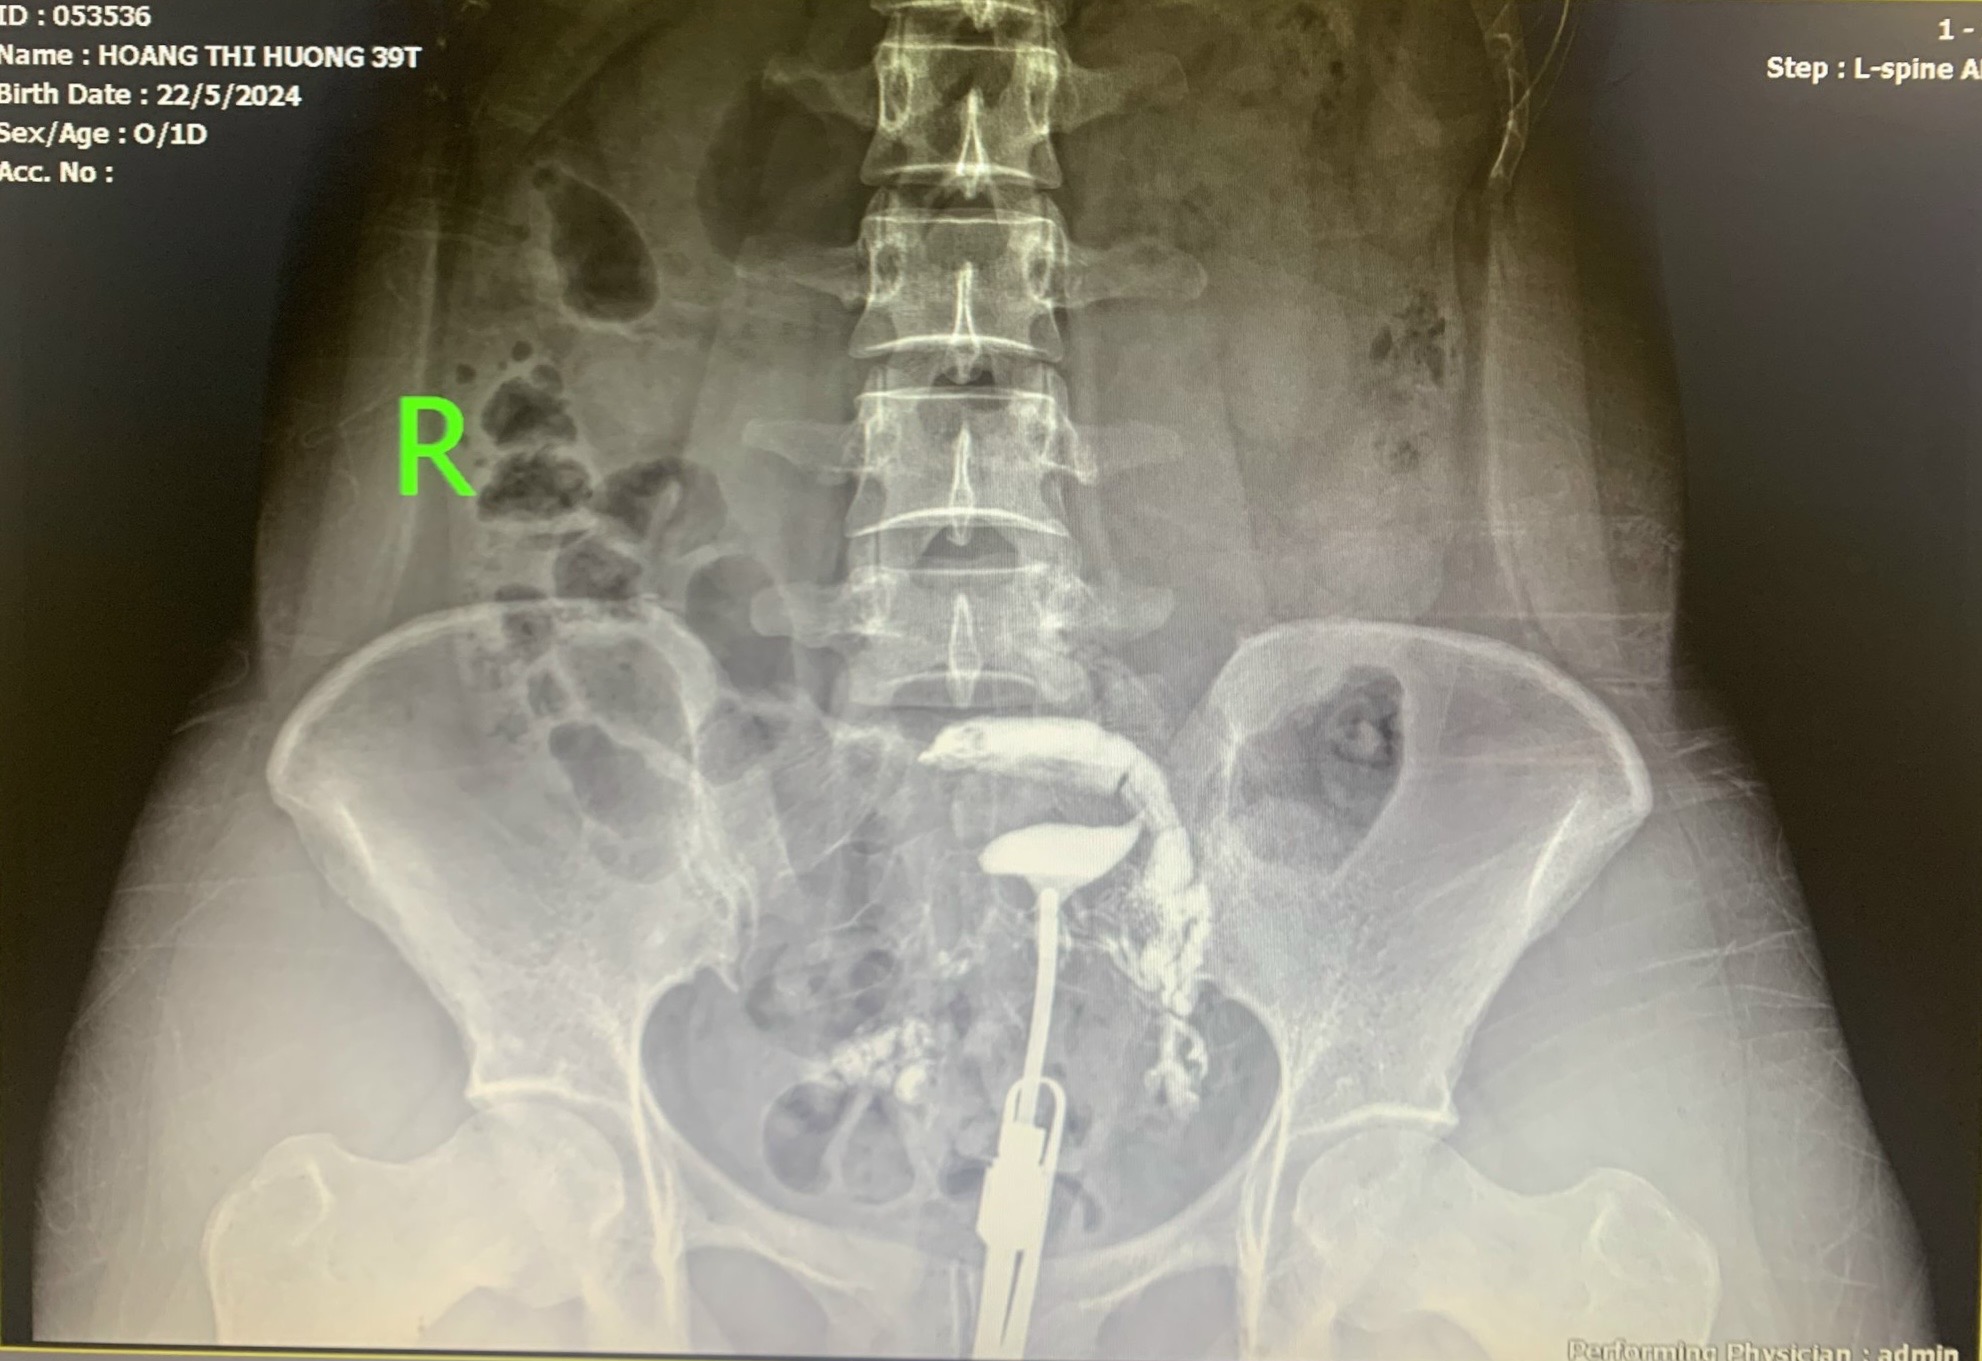

Hình ảnh chụp X-quang tử cung vòi trứng

Bác sĩ Bệnh viện Đa khoa Yên Bình Thái Nguyên đang thực hiện kỹ thuật chụp X-quang tử cung vòi trứng